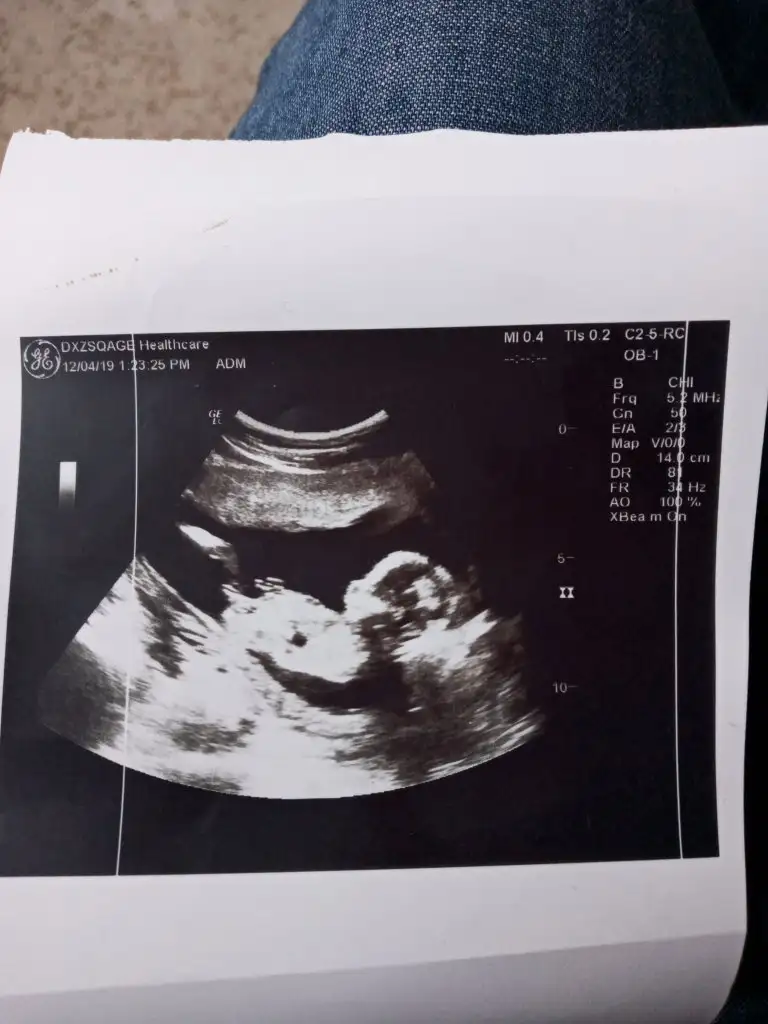

Kız gibi sanki 11 yada 12 hafta usg varmı13+4 günlükEki Görüntüle 2571462

11 yada 12 hafta olmalıSelam arkadaşlar cok merak ettim bende yorum alabilirmiyim ultrason fotomuza 10 haftalık

Kız gibiMerhaba benim için de tahminde bulunur musunuzz

12 haftalığıda atmıştım onada kız demiştin cnmKız gibi sanki 11 yada 12 hafta usg varmı

KAç haftalık bu usgde 11 yada 12 olmalıMeraba canım c doktor bir türlü soylemedi pozisyon alamadisen gorebilcenmi acaba

Kız bebeginiz burda kaç haftalıkEn son goruntusu bu ama burda da birsey belli olmuyor

Burada 16 haftalik tam.olarak nasil anladiniz pekiKız bebeginiz burda kaç haftalık